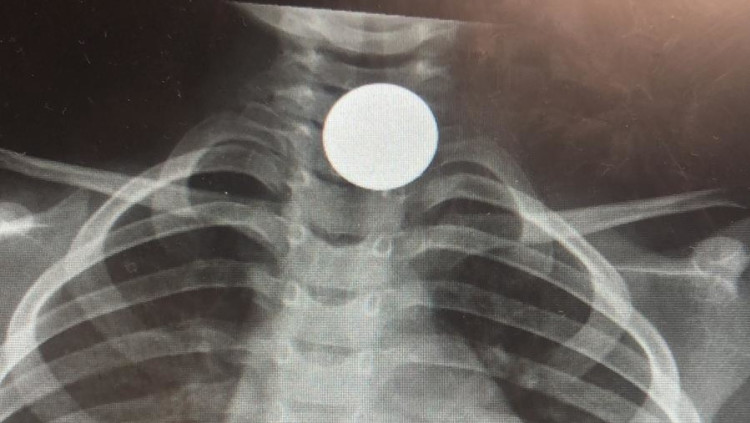

ילד בן 6 מהצפון בלע מטבע של 10 אגורות ופונה לבית חולים

מאיה גז